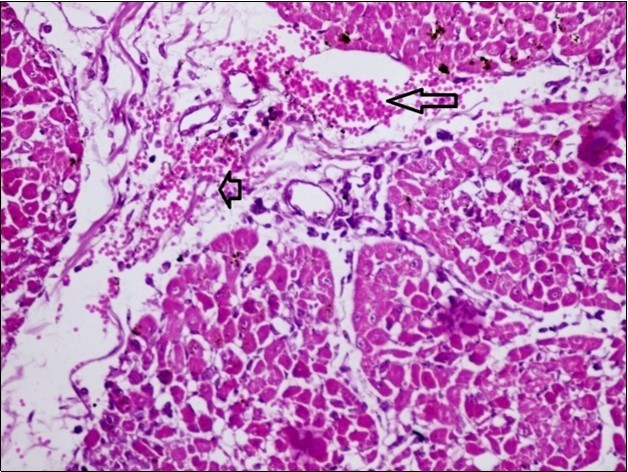

Figure 10.Heart (dead cattle less than 1 year old) showed area of extravasated blood with few inflammatory WBCs (arrows). (Hematoxylin and fuchsin X 40)

Figure 11.heart (dead cattle less than 1 year old) showed vesicular nuclei of myocytes which suffering hydropic degeneration. Some inflammatory cells (neutrophils, esinophils, lymphocytes) substitute an area of necrosis inside myocardium bundles (arrows). (H &E, X 40)